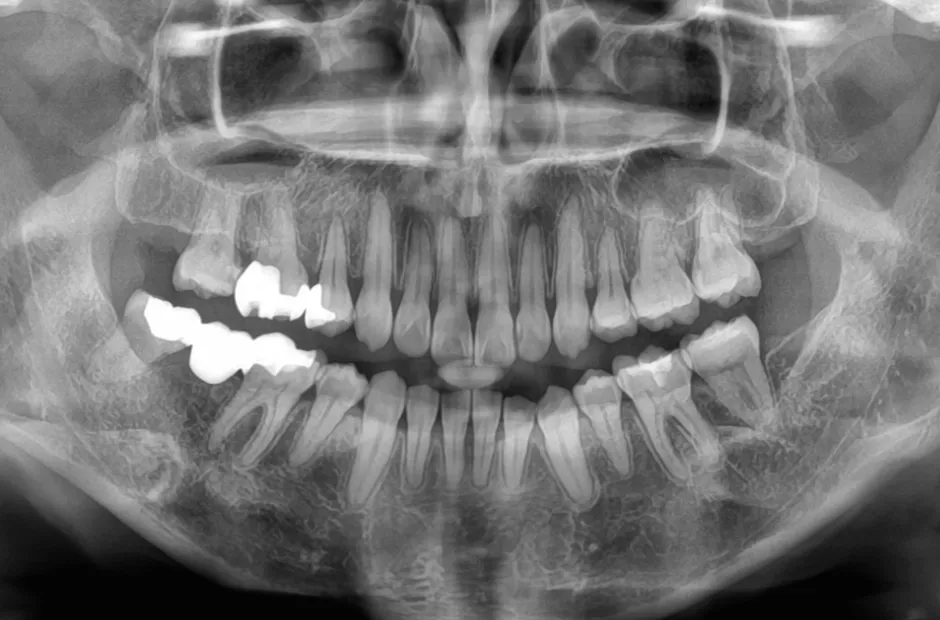

先天欠如(左右下2番)

| 診断名・主訴 | 過蓋咬合、出っ歯 |

|---|---|

| 年齢・性別 | 20歳・女性 |

| 治療期間・回数 | 2年 24回 |

| 治療に用いた主な装置 | 急速拡大 アンカー 2×4ワイヤー |

| 抜歯部位 | 左右上4番 |

| 治療費 | 70万円(税抜) |

| リスク・副作用 | 装置による違和感・疼痛・歯肉退縮・歯根吸収・虫歯のリスクなど |

治療前

治療中

治療後